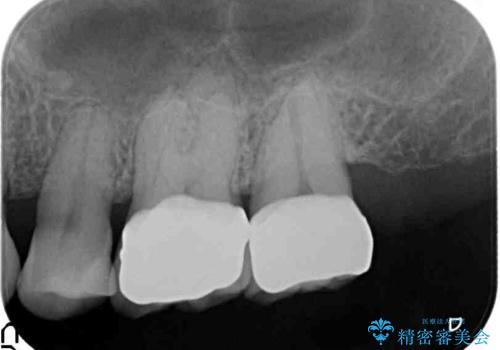

口の中の金属を外したい セラミッククラウンによる治療

- 笑った時に口の中で目立つ金属を外したい、虫歯の治療を再発の内容しっかりと行って欲しいと希望され来院されました。

銀歯・虫歯を丁寧に除去したのち精密なセラミック治療を行うことで長期的な予後を目指します。

銀歯をを外すだけでなく、セラミックを適合よく精密に製作することで長期的な予後を見込むことが可能になります。